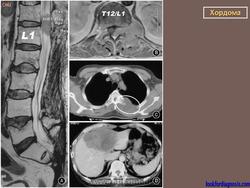

Хотя хордома может возникнуть в любом отделе позвоночного столба, наиболее излюбленными местами локализации этой опухоли являются 1-й шейный позвонок и пояснично-крестцовый отдел позвоночника. Это достаточно редкое заболевание. Чаще всего хордома возникает у мужчин среднего возраста. По данным рентгенографии, компьютерной томографии, магнитно-резонансной томографии можно поставить только предварительный диагноз. Для подтверждения диагноза необходимо проведение биопсии (забор кусочка опухолевой ткани с проведением микроскопического исследования). Лечение хирургическое. Прогноз зависит от размеров опухоли, наличия осложнений и общего состояния пациента.

Хордомы могут достигать больших размеров, особенно при их локализации в каудальном отделе позвоночника. Клиническая картина во многом зависит от направления роста хордомы. При росте в спинномозговой канал опухоль вызывает симптомы сдавления спинного мозга, конского хвоста и корешков нервов.

Рентгенологическая картина хордом характеризуется наличием очага деструкции, захватывающего ряд позвонков. Костный дефект представляется однородным, либо крупнокамерным за счет тонких костных полосок. Показаны боковые рентгенограммы крестца, на которых при хордоме определяется увеличение передне-заднего размера крестца за счет экспансивного роста опухоли. В отдельных случаях в опухоли прослеживаются небольшие костные включения, которые могут служить поводом для ошибочной диагностики тератом, особенно в детском возрасте. (В детском возрасте тератомы встречаются часто, их соотношение с хордомами, по данным М. В. Волкова, 60:2).